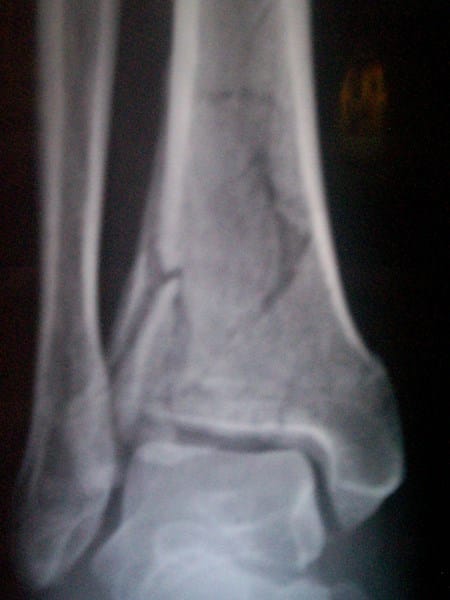

Antes que nada muchas gracias por su tiempo, no se cuanto tiempo, ni se que es lo que viene, como le digo tengo que ir a chilpancingo queda lejos y tengo cita cada mes, pero ahora iré hasta el mes y medio, para ganar tiempo, es decir al doctor voy a ir cuando tenga 9 o 10 semanas con el yeso pero no se cuanto tiempo debo de traerlo ud, cuanto tiempo opina que debo de traer el yeso aprox claro nuevamente muchas gracias por su atención le pongo las radiografías a la 5a semana

Cuanto tiempo cree uds que podre empezar a manejar para trabajar o cunto tiempo tardan este tipo de fracturas nuevamente mil gracias

Bien el tiempo es relativo pero 8 semanas podría ser suficiente dependiendo de las condiciones, que como máximo pueden llegar a 12

Manejar aun es muy pronto, hará falta rehabilitación, y más tiempo aun

Cuidarte va para largo